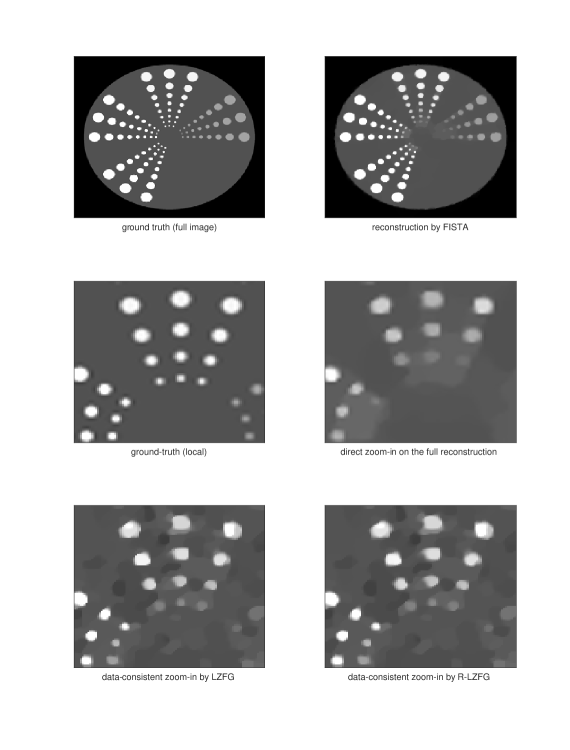

and we take the logarithm for the linearization of the measurements. We choose a low measurement energy with and the forward operator for low-dose CT example; while and for sparse-view CT example. We run all the experiments here in MATLAB R2020b. Given the measurement and full operator, we solve a TV-regularized least-squares optimization problem by FISTA and get a global estimate of the ground truth. As we can observe, the reconstructed images have a reasonable global quality but could oversmooth some of the local areas which may need to be refined and zoomed in. In this example, we seek to zoom-in 4 times larger a by block of a by image. Hence, the global iterative superresolution of the whole image will be at least 25 times more computationally expensive than our approach in this setting. Direct zoom-in on this block would often have poor performance since it does not re-utilize the measurement data. We then test our LZFG and R-LZFG, both using TV-regularization. We use the MATLAB imresize function as the up-sampling and down-sampling operators, with the default bicubic interpolation.

In Figures 2 and 3 we present two examples of local zoom-in. We can observe from the numerical results that our method can indeed recover the details of the local blocks in high quality. The direct zoom-in from the first-stage reconstruction fails to recover local details missed from the first-stage reconstruction since it does not utilize the measurement data, demonstrating the importance of data consistency in local zoom-in of medical images. We present the convergence curves of LZFG and R-LZFG in Figure 1 reporting the PSNR results towards the zoomed-in ground-truth image. From the PSNR result, we can observe that our methods provide significantly improved reconstruction accuracy (around 2 to 5 dB better) compared to the direct approach, which does not take into account the measurement data. Meanwhile, we also observe that the R-LZFG with adaptive restart can further improve the convergence performance in the final stage of the LZFG as shown in Figure 1, leading to a slight increase in PSNR within our computational budget.